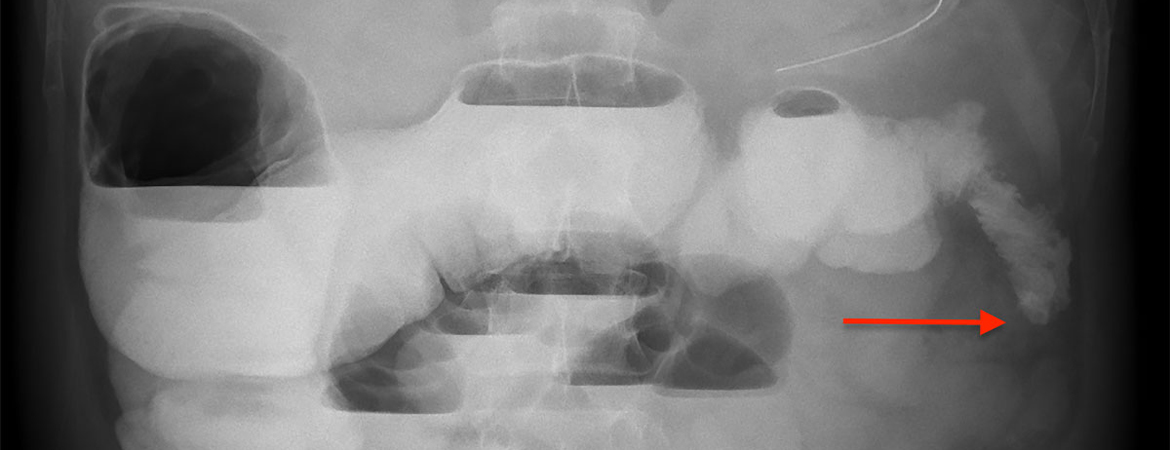

We report a case of a 42-year-old male who presented a hemorrhagic shock due to spontaneous rupture of an ascending branch of the left colic artery. The coexisting presence of multiple abdominal vascular abnormalities suggested the diagnosis of vEDS, later confirmed by the discovery of a new missense mutation in the COL3A1 gene with pathogenic significance. The post-operative course was marked by a mechanical ileus caused by an ischemic stenosis of the descending colon. Failure of conservative management and the well-known risk of colonic perforation in these patients led to the decision to perform a diverting ileostomy.